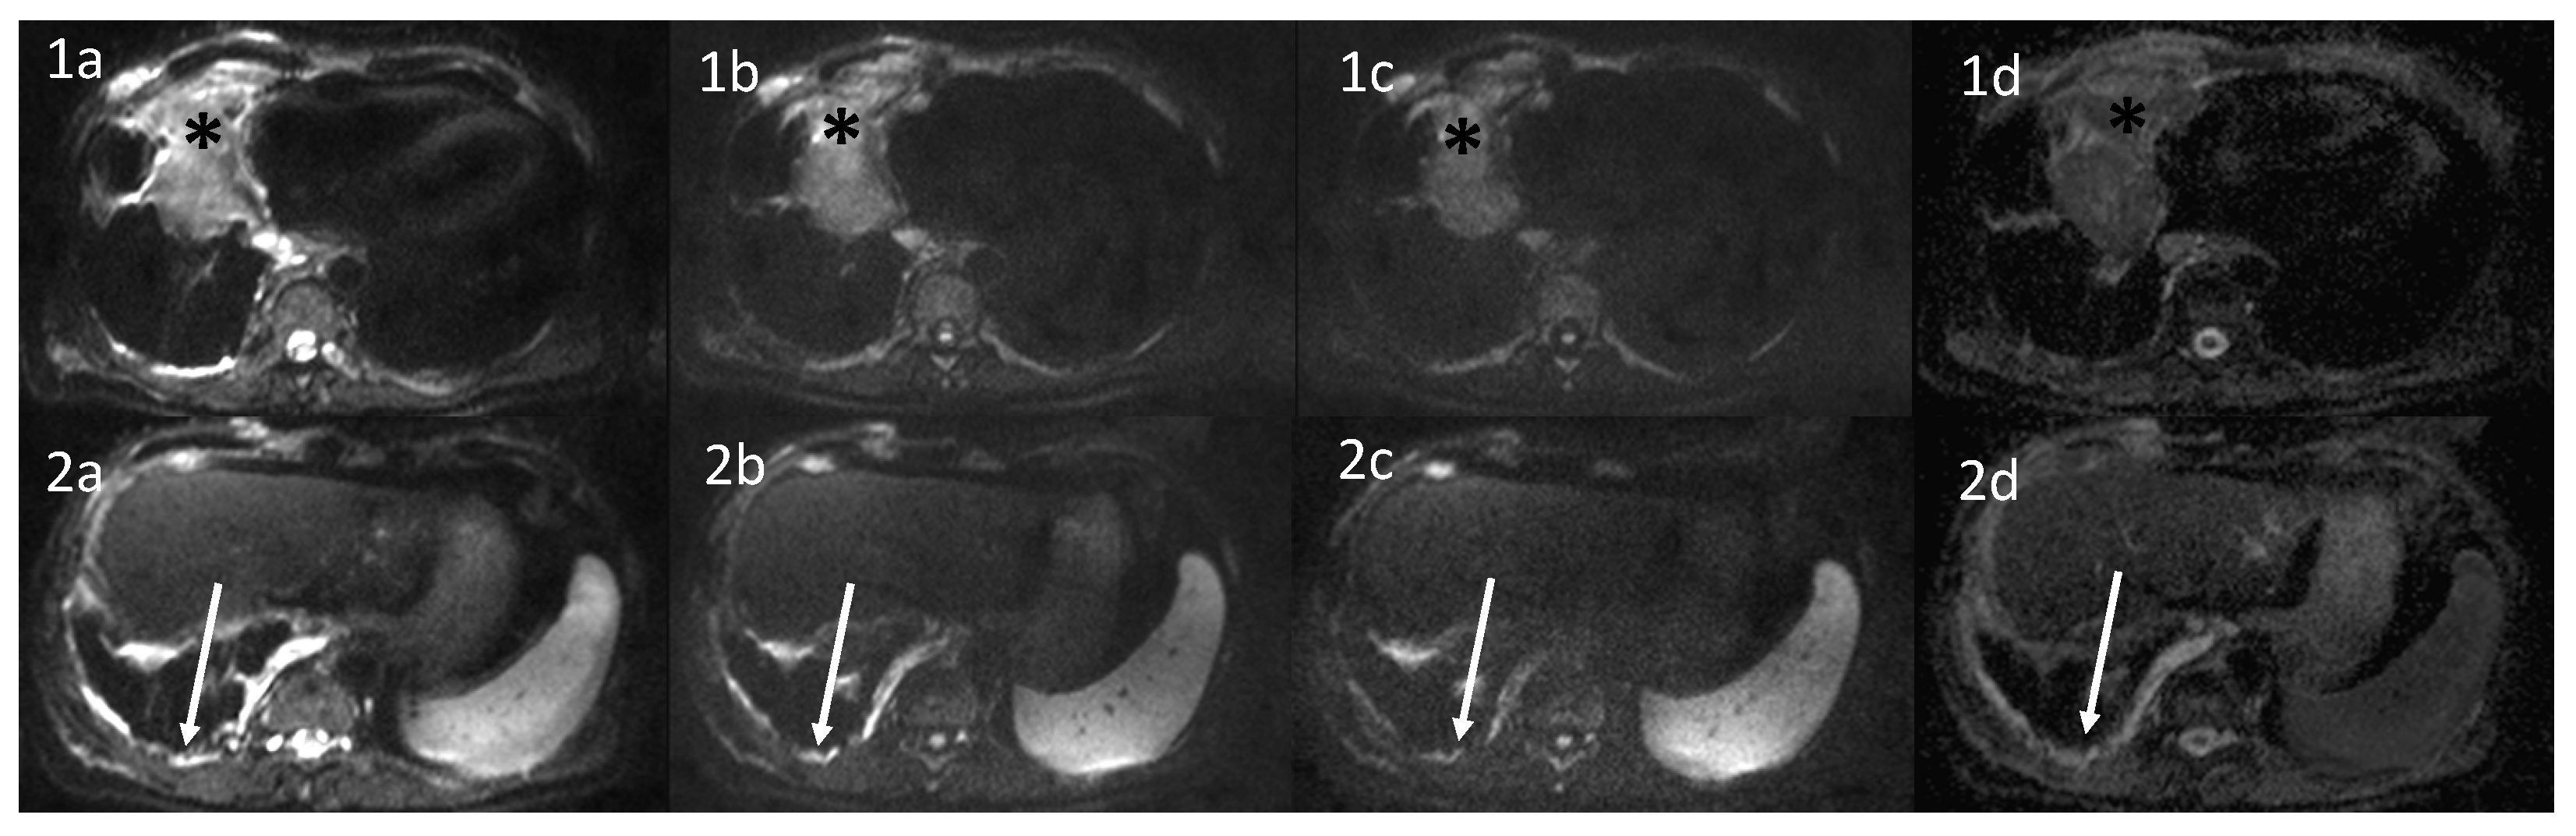

4.2.3. Diffusion-Weighted Imaging and Apparent Diffusion Coefficient

DWI-Visual Assessment